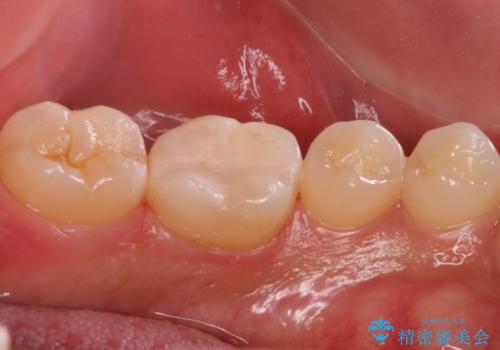

奥歯が欠けた セラミックインレーでの治療

- 奥歯が欠けたとのことで来院されました。

白い詰め物をご希望されたため、セラミックインレーでの治療を行います。

治療前後で比べると、詰め物と歯の間のすき間もなくなりセラミックインレーの適合の良さが伺えます。